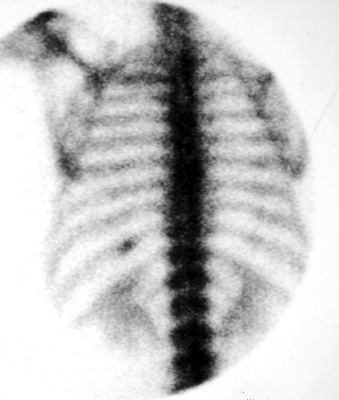

Bone scans can be used to localized specific lesions for biopsy. This is most often used to localize rib abnormalities. The position of the lesion is marked on the skin using a lead marker. After the portion of the bone has been removed, the piece can be reimaged to confirm that the abnormal portion of the bone was removed.

Note the lesion in the posterior left 10th rib.